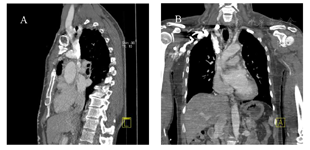

患者男,66岁,胸壁腹壁表浅静脉曲张半年,脸肿1个月余,随后行上腔静脉CT血管成像。

对比剂延扩张的胸壁以及腹壁表浅静脉,分别回流至双侧髂静脉,顺下腔静脉回流至心脏。其中奇静脉和肋间静脉也有扩张和对比剂充盈。上腔静脉中段显示局限性狭窄,接近闭塞,致使大量回流静脉扩张并逆流至髂静脉回流至心脏。